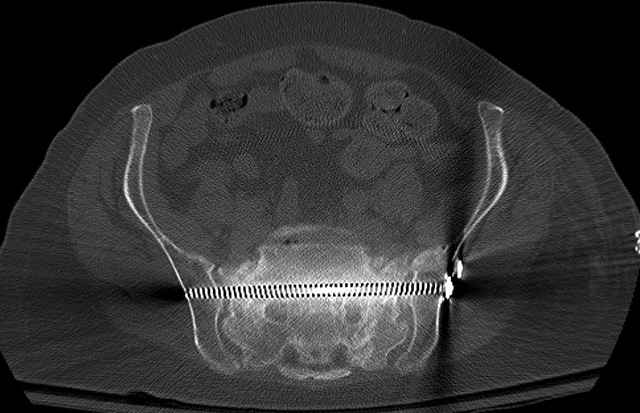

Pelvic CT Scan - 3 Months After Fall

Sacral Injuries

Ramus Fractures

Percutaneous Fixation

(B) Ramus-Retrograde

2 TransIliac-TransSacral

Upper Segment

mlcr